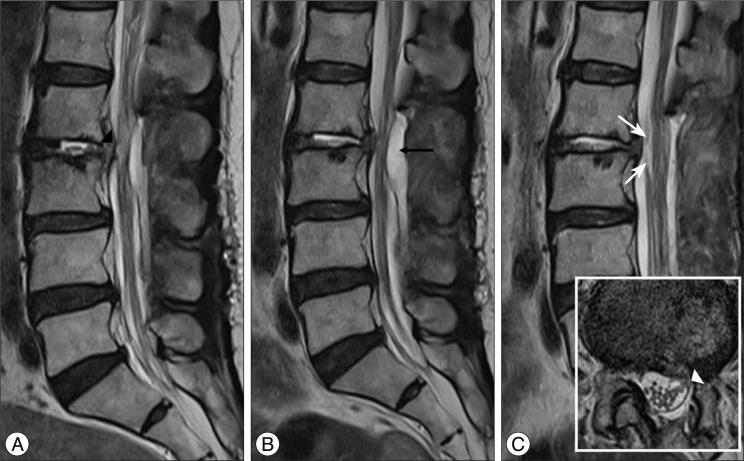

The authors report 2 cases of nerve root herniation after discectomy of a large lumbar disc herniation caused by an unrecognized dural tear. Patients complained of the abrupt onset of radiating pain after lumbar discectomy. Magnetic resonance imaging showed cerebrospinal fluid signal in the disc space and nerve root displacement into the disc space. Symptoms improved after the herniated nerve root was repositioned. Clinical symptoms and suggestive radiologic image findings are important for early diagnosis and treatment.

作者报告了2例因未识别的硬脊膜撕裂导致大的腰椎间盘突出症行椎间盘切除术后神经根疝的病例。患者在腰椎间盘切除术后出现突发的放射性疼痛。磁共振成像显示椎间盘间隙有脑脊液信号,神经根移位至椎间盘间隙。将疝出的神经根复位后症状改善。临床症状和提示性的影像学表现对早期诊断和治疗很重要。